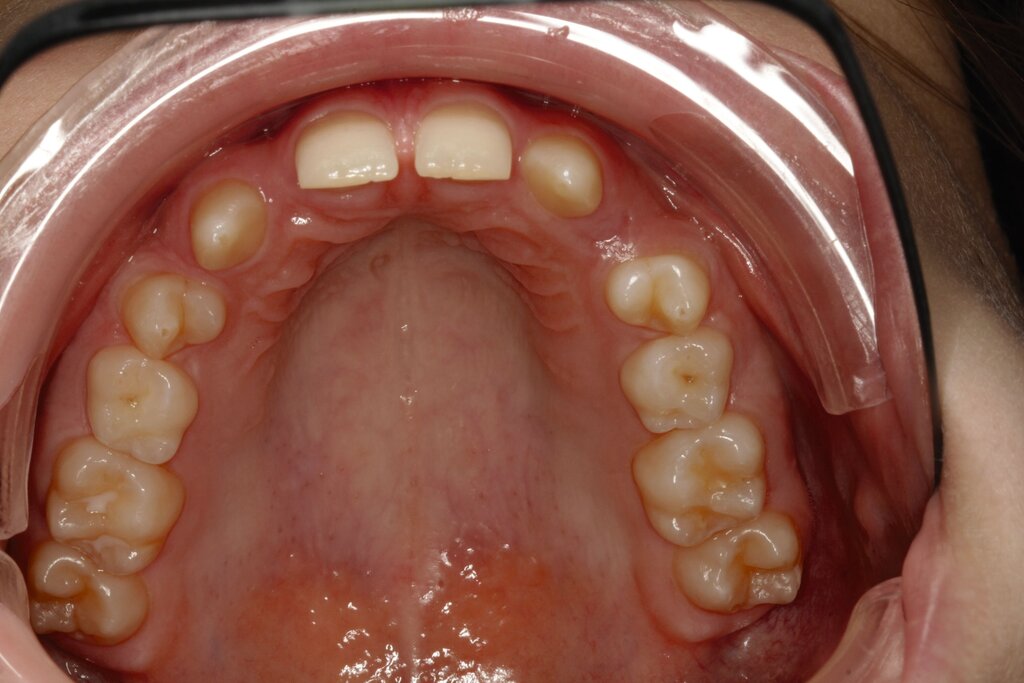

Bei dem gut zwölfjährigen Mädchen sind die seitlichen oberen Schneidezähne (Zähne 12 und 22) nicht angelegt. Zusätzlich zeigten sich verlagerte zweite obere Prämolaren.

Im vorliegenden Fall stand der Zahn 23 bereits im Mesialstand bei hoher Lachlinie und tendenziell konkavem Lippenprofil. Bezüglich Morphologie und Farbe waren die Zähne 13 und 23 nicht ausgeprägt eckzahntypisch. Es bestand kein Platzmangel im Gegenkiefer. Die Patientin war bei der Erstdiagnose 12,5 Jahre alt und im Wechselgebiss der zweiten Phase mit atypischer Durchbruchreihenfolge. Es bestand eine geringfügige Klasse II. Der Overjet war vergrößert bei vertikaler Wachstumstendenz, der Overbite war um circa einen Millimeter vergrößert aufgrund der geringfügigen Steilstellung der Oberkiefer-Front. Es bestand der Verdacht auf Nichtanlage der Weisheitszähne, 15 und 25 waren verlagert.

Daher wurde ein Lückenmanagement mit Lückenschluss in der Oberkiefer-Front und Lückenöffnung mesial 16 und 26 außerhalb der ästhetischen Zone angestrebt. Eine implantatprothetische Versorgung kam aufgrund des jungen Alters der Patientin nicht infrage. Die Autotransplantation eines Prämolaren war ebenfalls ausgeschlossen, da kein Engstand und keine Indikation zur Ausgleichsextraktion bestanden.